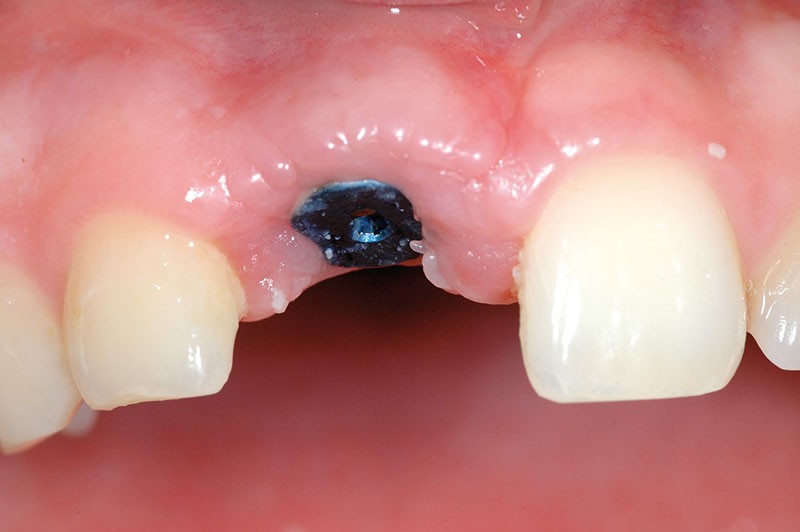

Après analyse et discussion avec la patiente, nous décidons de ne pas retirer l’implant, ce qui entraînerait un dégât osseux important lors de la dépose.

Nous proposons de retirer la couronne et le pilier implantaire, d’effectuer une greffe de tissu conjonctif enfouie afin d’améliorer le volume du tissu kératinisé péri-implantaire [5] et de procéder à la pose d’une couronne provisoire transvissée (fig. 3a à h).